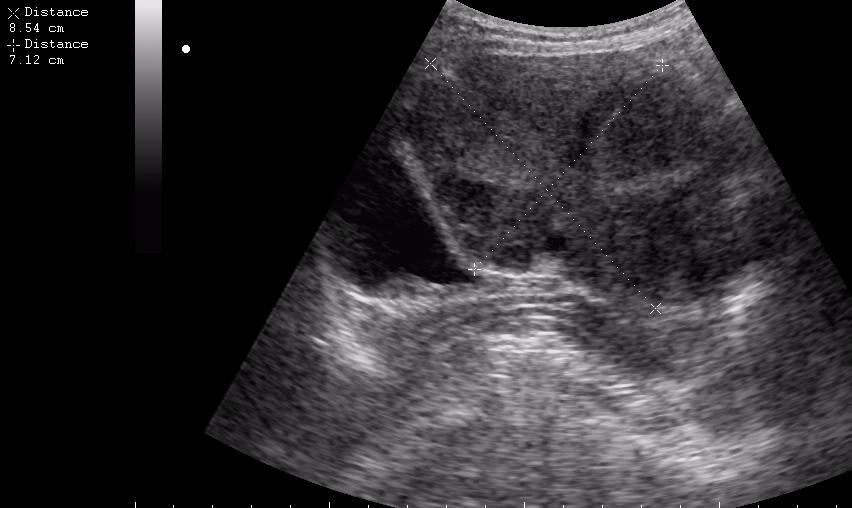

ещё раз - это матка 23-летней девушки. то есть, ВСЁ это, то что Вы видите, да-да, на весь экран - это матка.

Диагноз - фиброматоз. направлена строго на север и налево. к соседям. (онкодиспансер)

ну вот куда здесь ставить бодимаркер и какой?